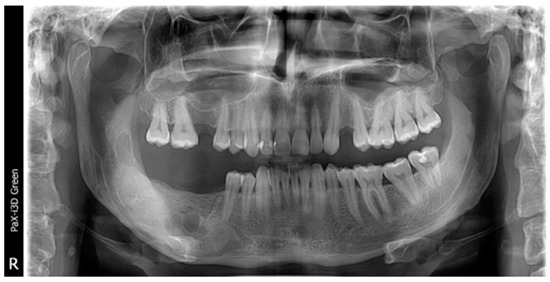

2. Case Presentation